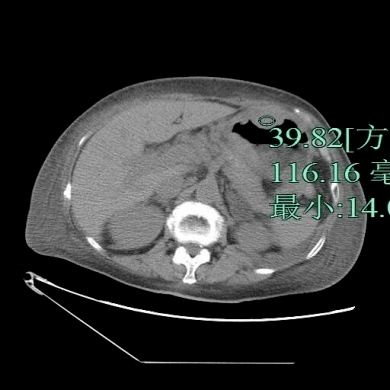

患者 , 女性 , 87岁 , 因咳嗽气急1周、发热4天入院 。 查体:未见明显异常 。 影像检查如下 , 以下哪个诊断最有可能?

文章图片

A.胃癌

B.肥厚性胃炎

C.淋巴瘤

D.神经内分泌肿瘤

E.间质瘤